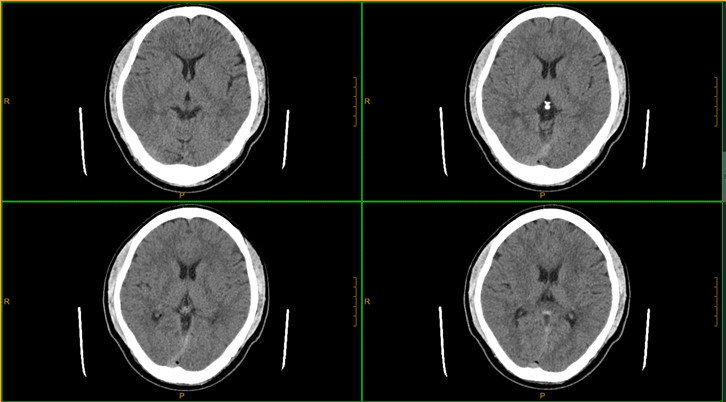

·0.275mm ultra-thin layer scanning can clearly show the fine structures in the human body, such as inner ear and small pulmonary nodules

Clinical Gallery